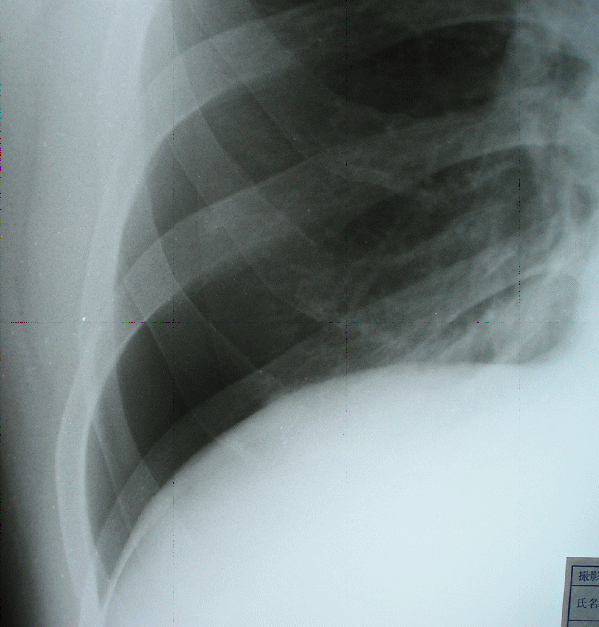

肺がしぼんでいる。

33歳 男性の気胸。

右胸の痛みで発見。